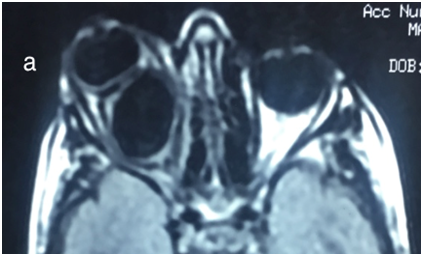

An orbital magnetic resonance imaging (MRI) revealed a well-defined cyst lesion sized 20×18×25 mm located in the intraconal space of the right orbit,hypointense on T1 weighted,hyper intense on T2 weighted, with marginal ring enhancement after an IV injection of gadolinium ethoxybenzyldiethylenetriaminepentaacetic(Figure 3).

The orbital MRI showsahypo intense cystic lesion on T1 weighted, hyper intense on T2 weighted, with marginal ring enhancement. The diagnosis of cyst capsule and intraconal lesions is facilitated with fat suppression.20

Also, orbital MRI has proved to be a very useful for the differential diagnosis that include dermoid and epidermoid cyst, chronic hematic orbital cysts, orbital abscess, congenital cyst, mucocele, lymphangioma, teratoma and other orbital cystic lesions.9,21